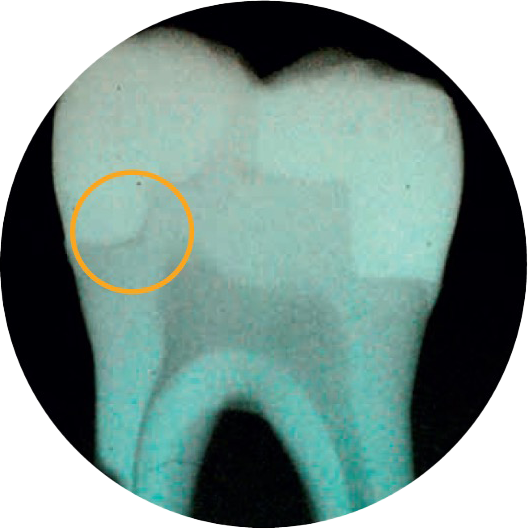

Остаются зазоры?

Двое из трех стоматологов считают адаптацию к полости наиболее важной частью успешной реставрации 2.

Вам непременно понравится текучий композит объемного внесения SDR Plus!

SDR Plus считается прорывом в стоматологии: этот текучий композит объемного внесения можно вносить слоем до 4 мм. Свойство самовыравнивания и минимальный полимеризационный стресс гарантируют оптимальную адаптацию к полости и отсутствие пустот.